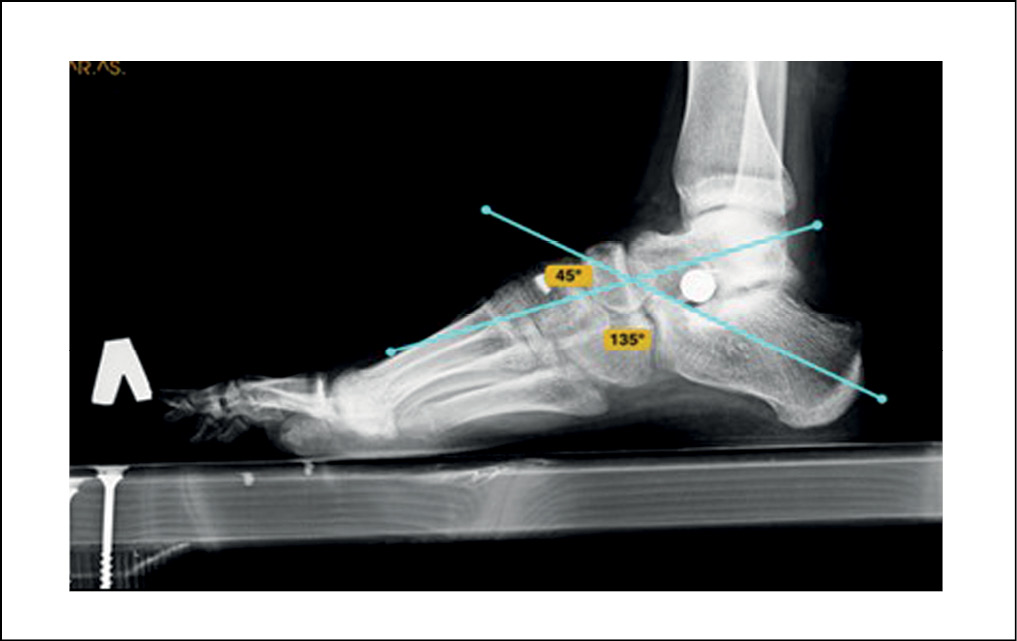

Рентгенография стоп под нагрузкой: оценивались такие показатели, как угол продольного свода стопы, который образуется пересечением двух касательных – одна к подошвенной поверхности пяточной кости, другая – к подошвенной поверхности первой плюсневой кости (в норме угол продольного свода стопы равен 125–130°, высота свода > 35 мм); угол Кайта, образованный пересечением продольных осей таранной и пяточной костей (норма 25–55 градусов); угол Meary – между первой плюсневой и таранной костью (в норме не должен превышать 4 градусов (рисунки 1, 2).

Рисунок 2. Рентгенограмма правой стопы в боковой проекции под нагрузкой. / Figure 2. X-ray of the right foot in the lateral projection under load.